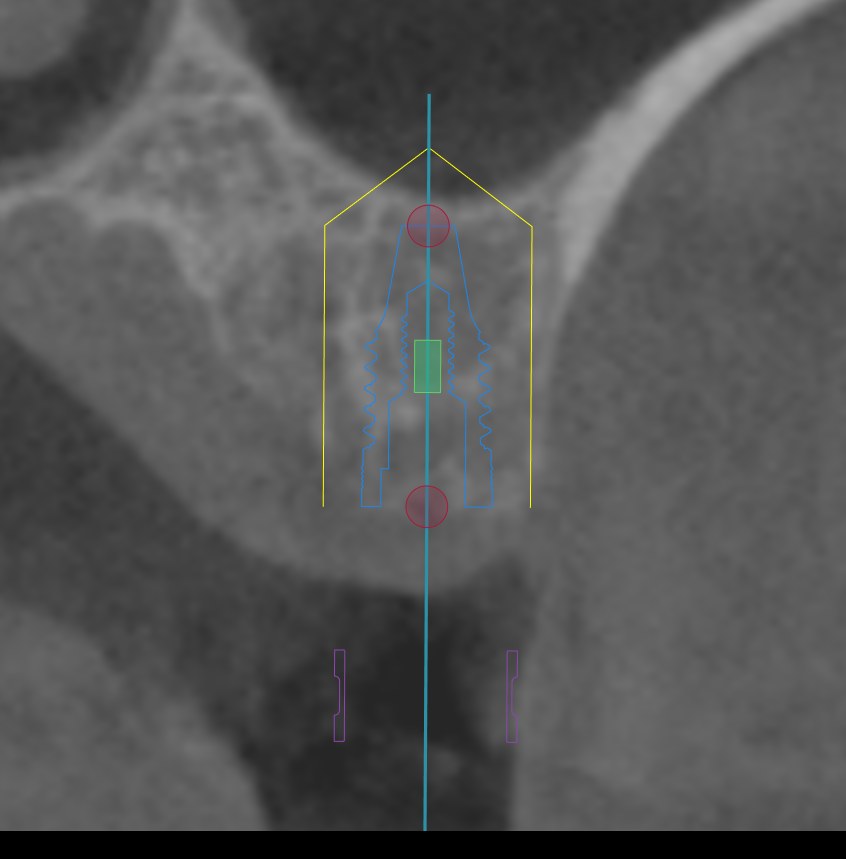

CT撮影

埋入位置を決めるための装置(ラジオグラフィックガイド)を口腔内に入れCTを撮影します。

埋入ガイド

CT画像上にて決定した埋入位置で製作された埋入ガイド。正確でスムーズな手術を行えます。

CTシミュレーション

CTデータをインプラント解析ソフトに入れ、手術のシミュレーションをします。

・骨の状態を確認し、骨造成が必要か見極めます。

・シミュレーションでインプラントが可能か確認し、インプラントのサイズを調べます。